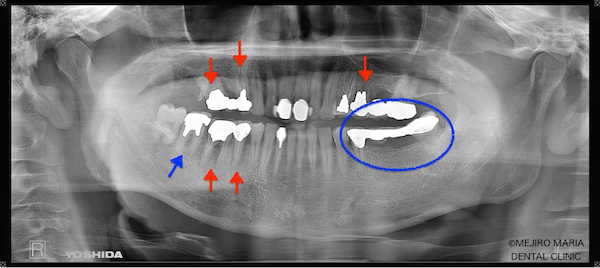

まずは、歯周組織検査を含めた口腔内診査、レントゲン写真の撮影により、保存できる歯牙と、抜歯をせざるを得ない歯牙などを選定しました。

当院では精密根管治療により、ほとんどの歯牙の保存が可能なことから、最初の段階では、明らかな歯根破折が確認される場合のみ抜歯の診断をしています。精密根管治療を行っても、歯牙保存による費用対効果が低いと考えられる場合は、その都度患者様と相談の上、歯牙を保存するか抜歯するか選択していきます。

今回の症例では、歯根破折していた5本の歯牙(下の写真・赤矢印)に対して、抜歯を提案した。また、診断用WaxUp(ワックスアップ)を行ったところ左下のブリッジ(青丸)と右下(青矢印)の噛み合わせ平面が乱れており、咬合に負担をかけていることが予想されました。そのため、最終的にそれらの不調和を改善し、適切な噛み合わせにすることをゴールとして治療を開始しました。